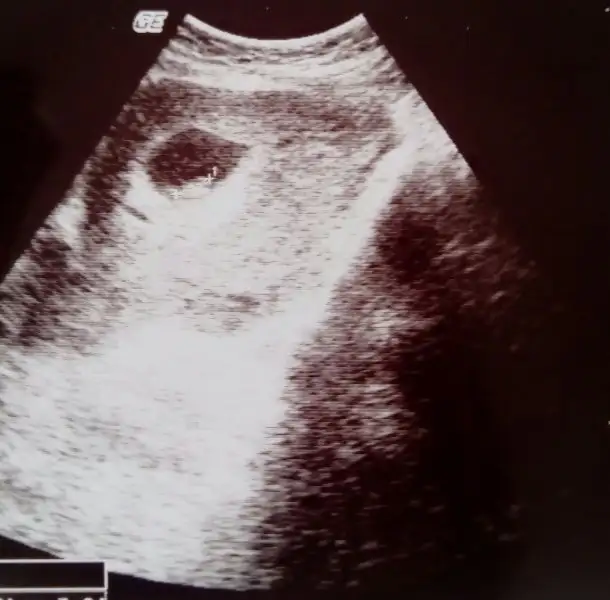

Bu da çok erken bı ultrason daha bebişin görünmüyor sadece kese varmış o zamanlar. 6-7 haftalık bir görüntü varsa onu at en iyisi